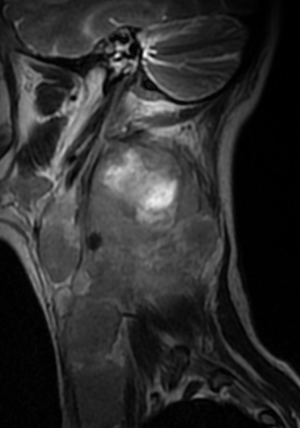

МР-диагностика новообразований мягких тканей шеи

- Выявление опухолевого поражения данной локализации